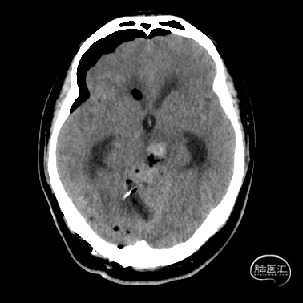

术后当天CT

术后1周CT复查